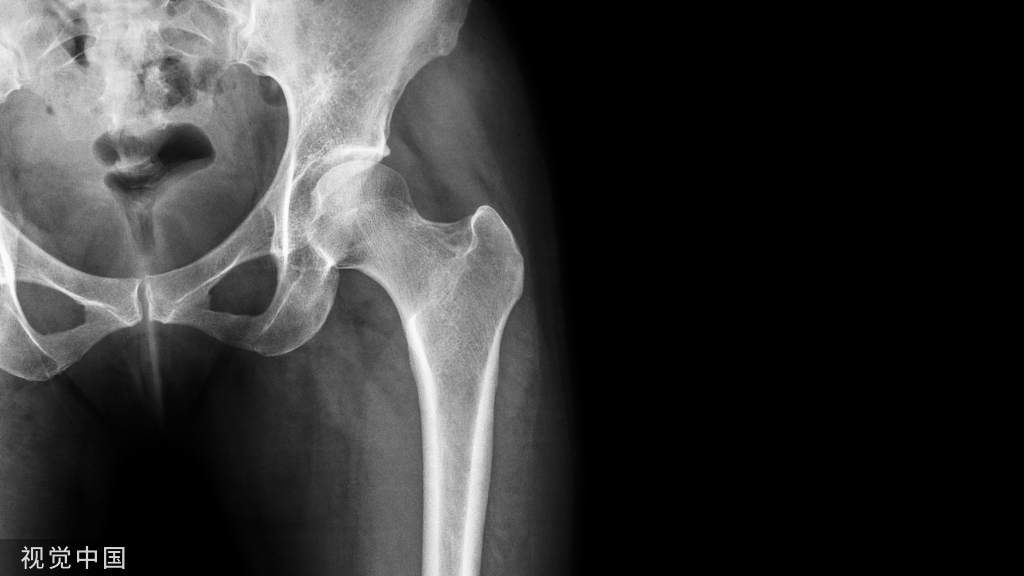

• X—RAY 踝关节正侧位(必要时应加照踝穴位)

应力位片